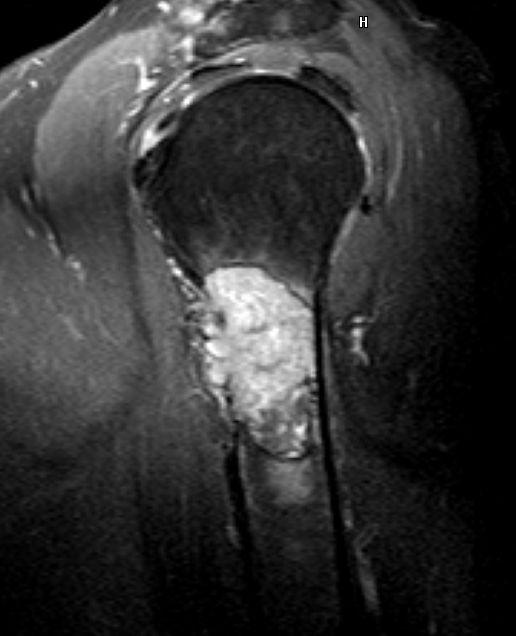

66-jähriger Mann, der vor 8 Jahren ein Prostata - Ca hatte.

Gleason 6, PSA 7,7: wait and watch. Vor 4 Jahren Radikaloperation abgebrochen

wegen LK-Metastasen rechts iliacal. Th.: Bicalutamid und Eligard. Vor 2 Jahren

PSA-Anstieg auf 7,5: RT Prostata+LA, dann Zytiga / Prednisolon, Denosumab. Jetzt

PSA 73,9 und schmerzhafte Rippenmetastasen.![]() |

![]() | |||||||||||||||||||